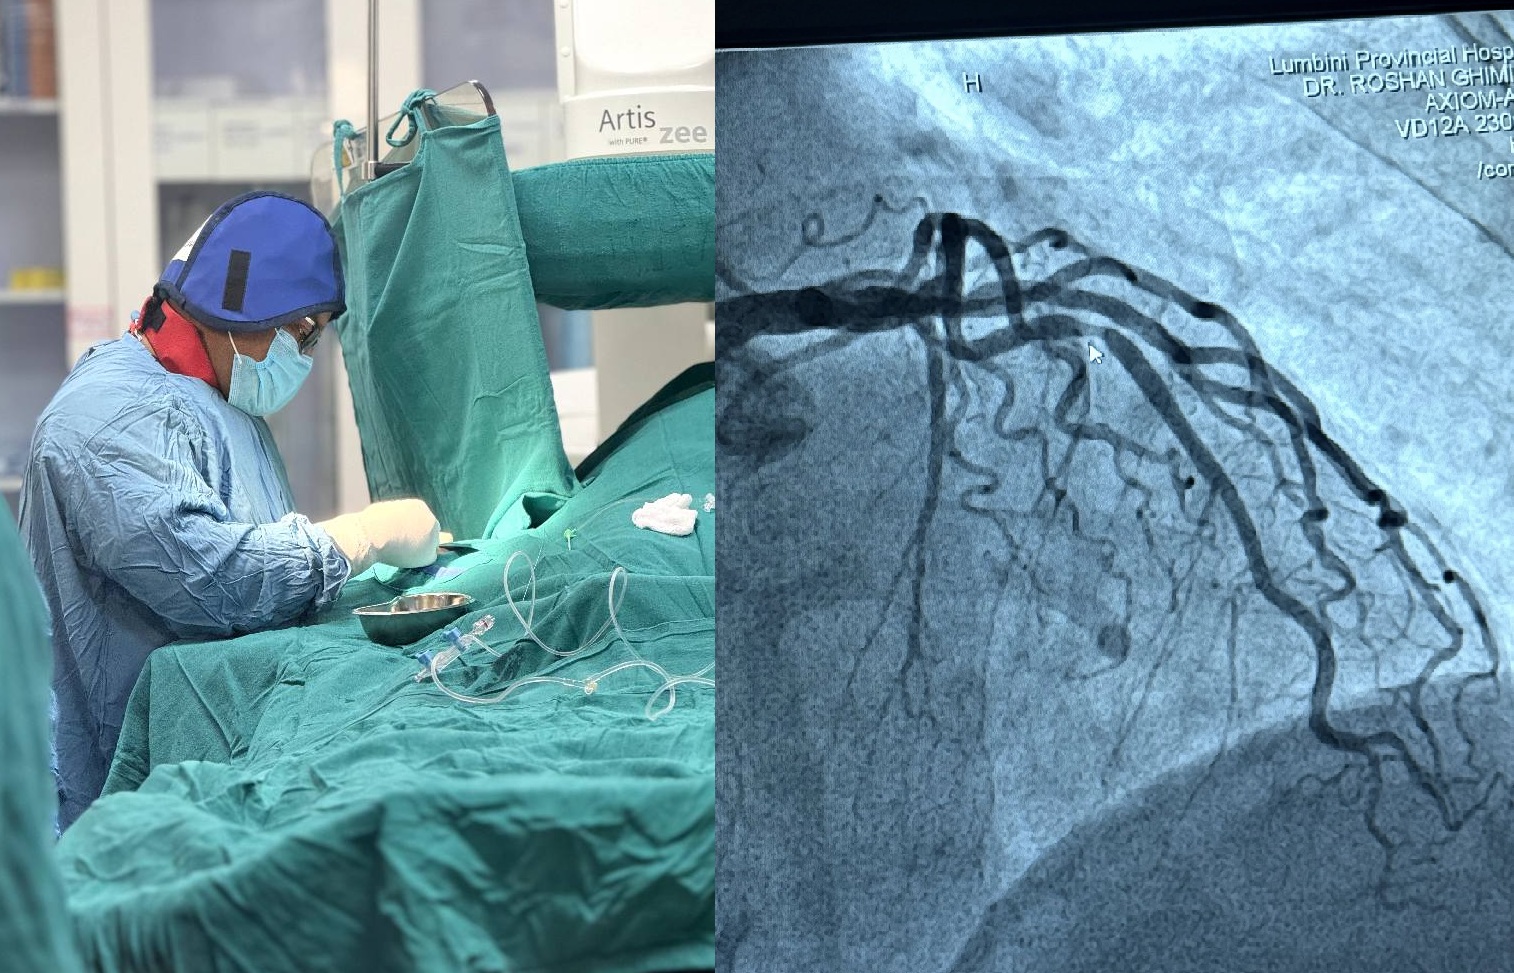

सफल भयो लुम्बिनी प्रादेशिकमा “एन्जियोप्लाष्टी”

बुटवल । लुम्बिनी प्रादेशिक अस्पताल बुटवलमा मुुटु सम्बन्धि जटिल समस्याको निराकरण गर्ने प्रयास सफल भएको छ । पहाडी जिल्ला र तराईका क्षेत्रहरुको प्रमुख ठूलो मानिने सरकारीस्तरको अस्पतालमा यसअघि मुुटु सम्बन्धि सेवा नहुँदा मुटु रोग भएका पीडित नागरिकहरु जिल्लाबाहिर जानुपर्ने बाध्यता थियो ।

पछिल्लोसमय स्वास्थ्यमा केही नयाँपन र सुधार भइरहेको अस्पतालमा मुटुमा जोडिएका रक्तसञ्चार नशाहरु ब्लक भएको समस्यालाई हात वा खुट्टाको नशाबाट प्रविधि हालेर मुुटुमा रहेका ब्लक भएका नशालाई खुलाउन जाली राख्ने प्रक्रिया (एन्जियोप्लाष्टी) गर्ने काम सोमबार (आज) सफल भएको अस्पतालका वरिष्ठ मुुटु रोग डाक्टर रोसन घिमिरेले बताए ।

उनले भने, म बुटवल आएपछि हालसम्म यो सेवा दिन खोजेपनि गर्न पाएको थिएन, ढिलै भएपनि आज पूरा गरेर छाडे । खुसी छु । डाक्टर घिमिरेले गरेको यो सेवा लुम्बिनी प्रादेशिक अस्पतालको लागि नयाँ सेवा मानिएको छ ।